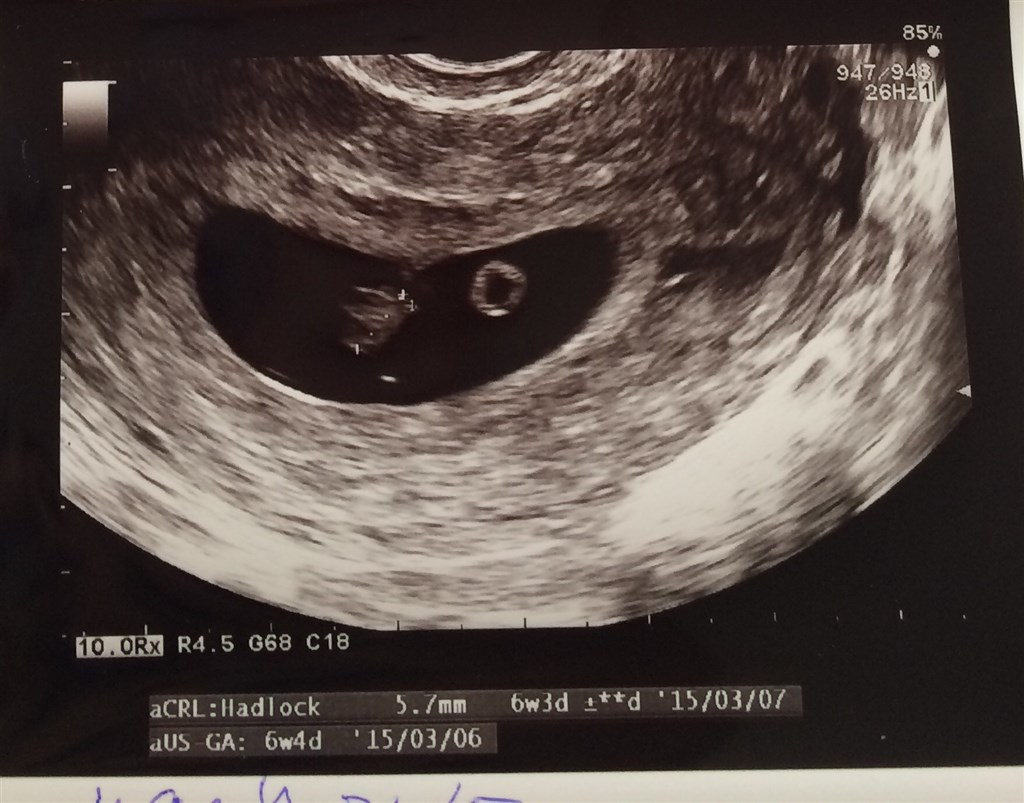

Her er mit billed hvor jeg er 6+3, men troede jeg var 7+3. Og det er 2 uger siden jeg blev scannet.

håber og krydser for dig :-)

Vedhæftede fotos (klik for at se i fuld størrelse)